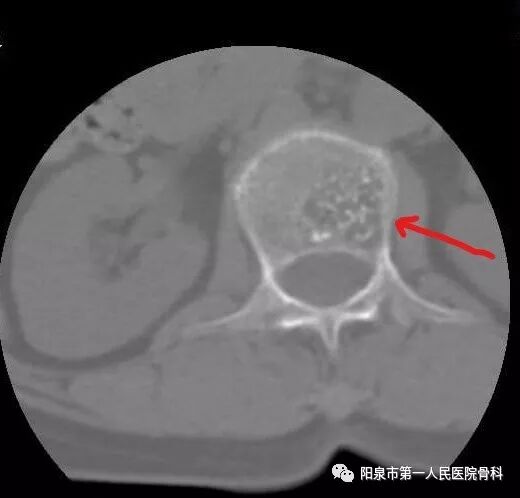

2.一些因椎体原发性肿瘤(如血管瘤)或转移性肿瘤而导致的椎体破坏也适合椎体成形术。由于转移性肿瘤而导致椎体破坏,疼痛症状明显又不能采用开放手术治疗的情况下,椎体成形术常常可以有效缓解局部疼痛症状而提高生活质量

下图红箭头所示为椎体因肿瘤而被破坏的表现。此时患者多会表现持续性加重的背部疼痛,严重影响日常活动。

椎体成型需要哪些器材椎体成形术概述_https://www.jmylbn.com_新闻资讯_第14张